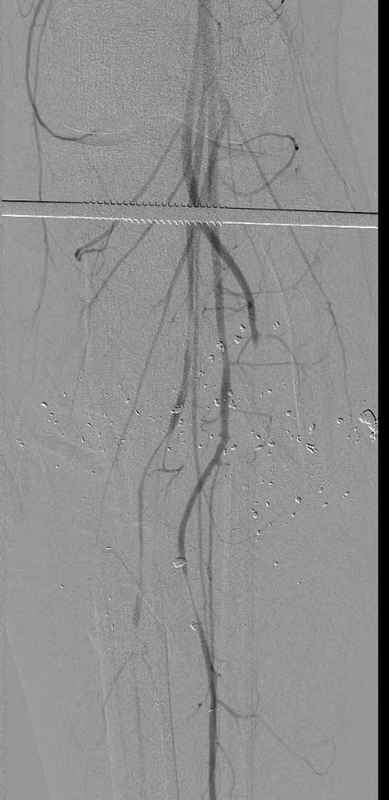

11.08.09 доставлен в операционную, Irrigation&Debridment c фиксацией Наружным Фиксатором и вакуумирование VAC; службой травмы пройзведена ангиография с негативным результатом. (снимки 1-10)

Имя     : 7 gsw tibia abgiography.jpg

Тип     : image/jpeg

Размер  : 26344 байтов

Описание: отсутствует

Url     : http://weborto.net:8080/pipermail/ortho/attachments/20090831/f744a2dd/attachment-0019.jpg

Вложение не в текстовом формате было извлечено…

Имя     : 8 gsw tibia abgiography_1.jpg

Url     : http://weborto.net:8080/pipermail/ortho/attachments/20090831/f744a2dd/attachment-0020.jpg